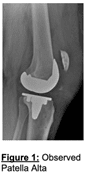

A 57-year-old male with a history of morbid obesity, bilateral total knee arthroplasty (TKA), and other medical conditions including hypertension, degenerative disc disease, and asthma, presented with a complete rupture of the left patellar tendon. The injury occurred six weeks after a left TKA, following a ground-level fall in his yard that resulted in a hyperflexed knee and a rapid eccentric contraction of the quadriceps. Examination revealed significant swelling, anterior knee tenderness, and a complete inability to actively extend the knee, with 0/5 strength in extension. Radiographs showed patella alta, suggesting a complete patellar tendon tear, while the femoral, tibial, and patellar components of the TKA remained well fixed. Additional patient factors complicated the case, including a history of long-term testosterone replacement therapy, steatosis of the liver, and prior surgeries, which may have influenced tissue quality and healing capacity. Objective findings included limited knee range of motion (extension lag of 4 degrees and flexion limited to 24 degrees), significant joint line edema (+9 cm), and adequate quadriceps activation despite the rupture.

The surgical procedure began with a midline knee incision to expose the quadriceps and patellar tendons, confirming a complete tear of the patellar tendon with resultant patella alta. To address the significant tension on the tendon, a V-Y quadricepsplasty was performed, allowing for approximately 2 cm of tendon lengthening. The patellar tendon was repaired using a combination of Krackow sutures and suture anchors to reattach the tendon securely to the inferior pole of the patella.